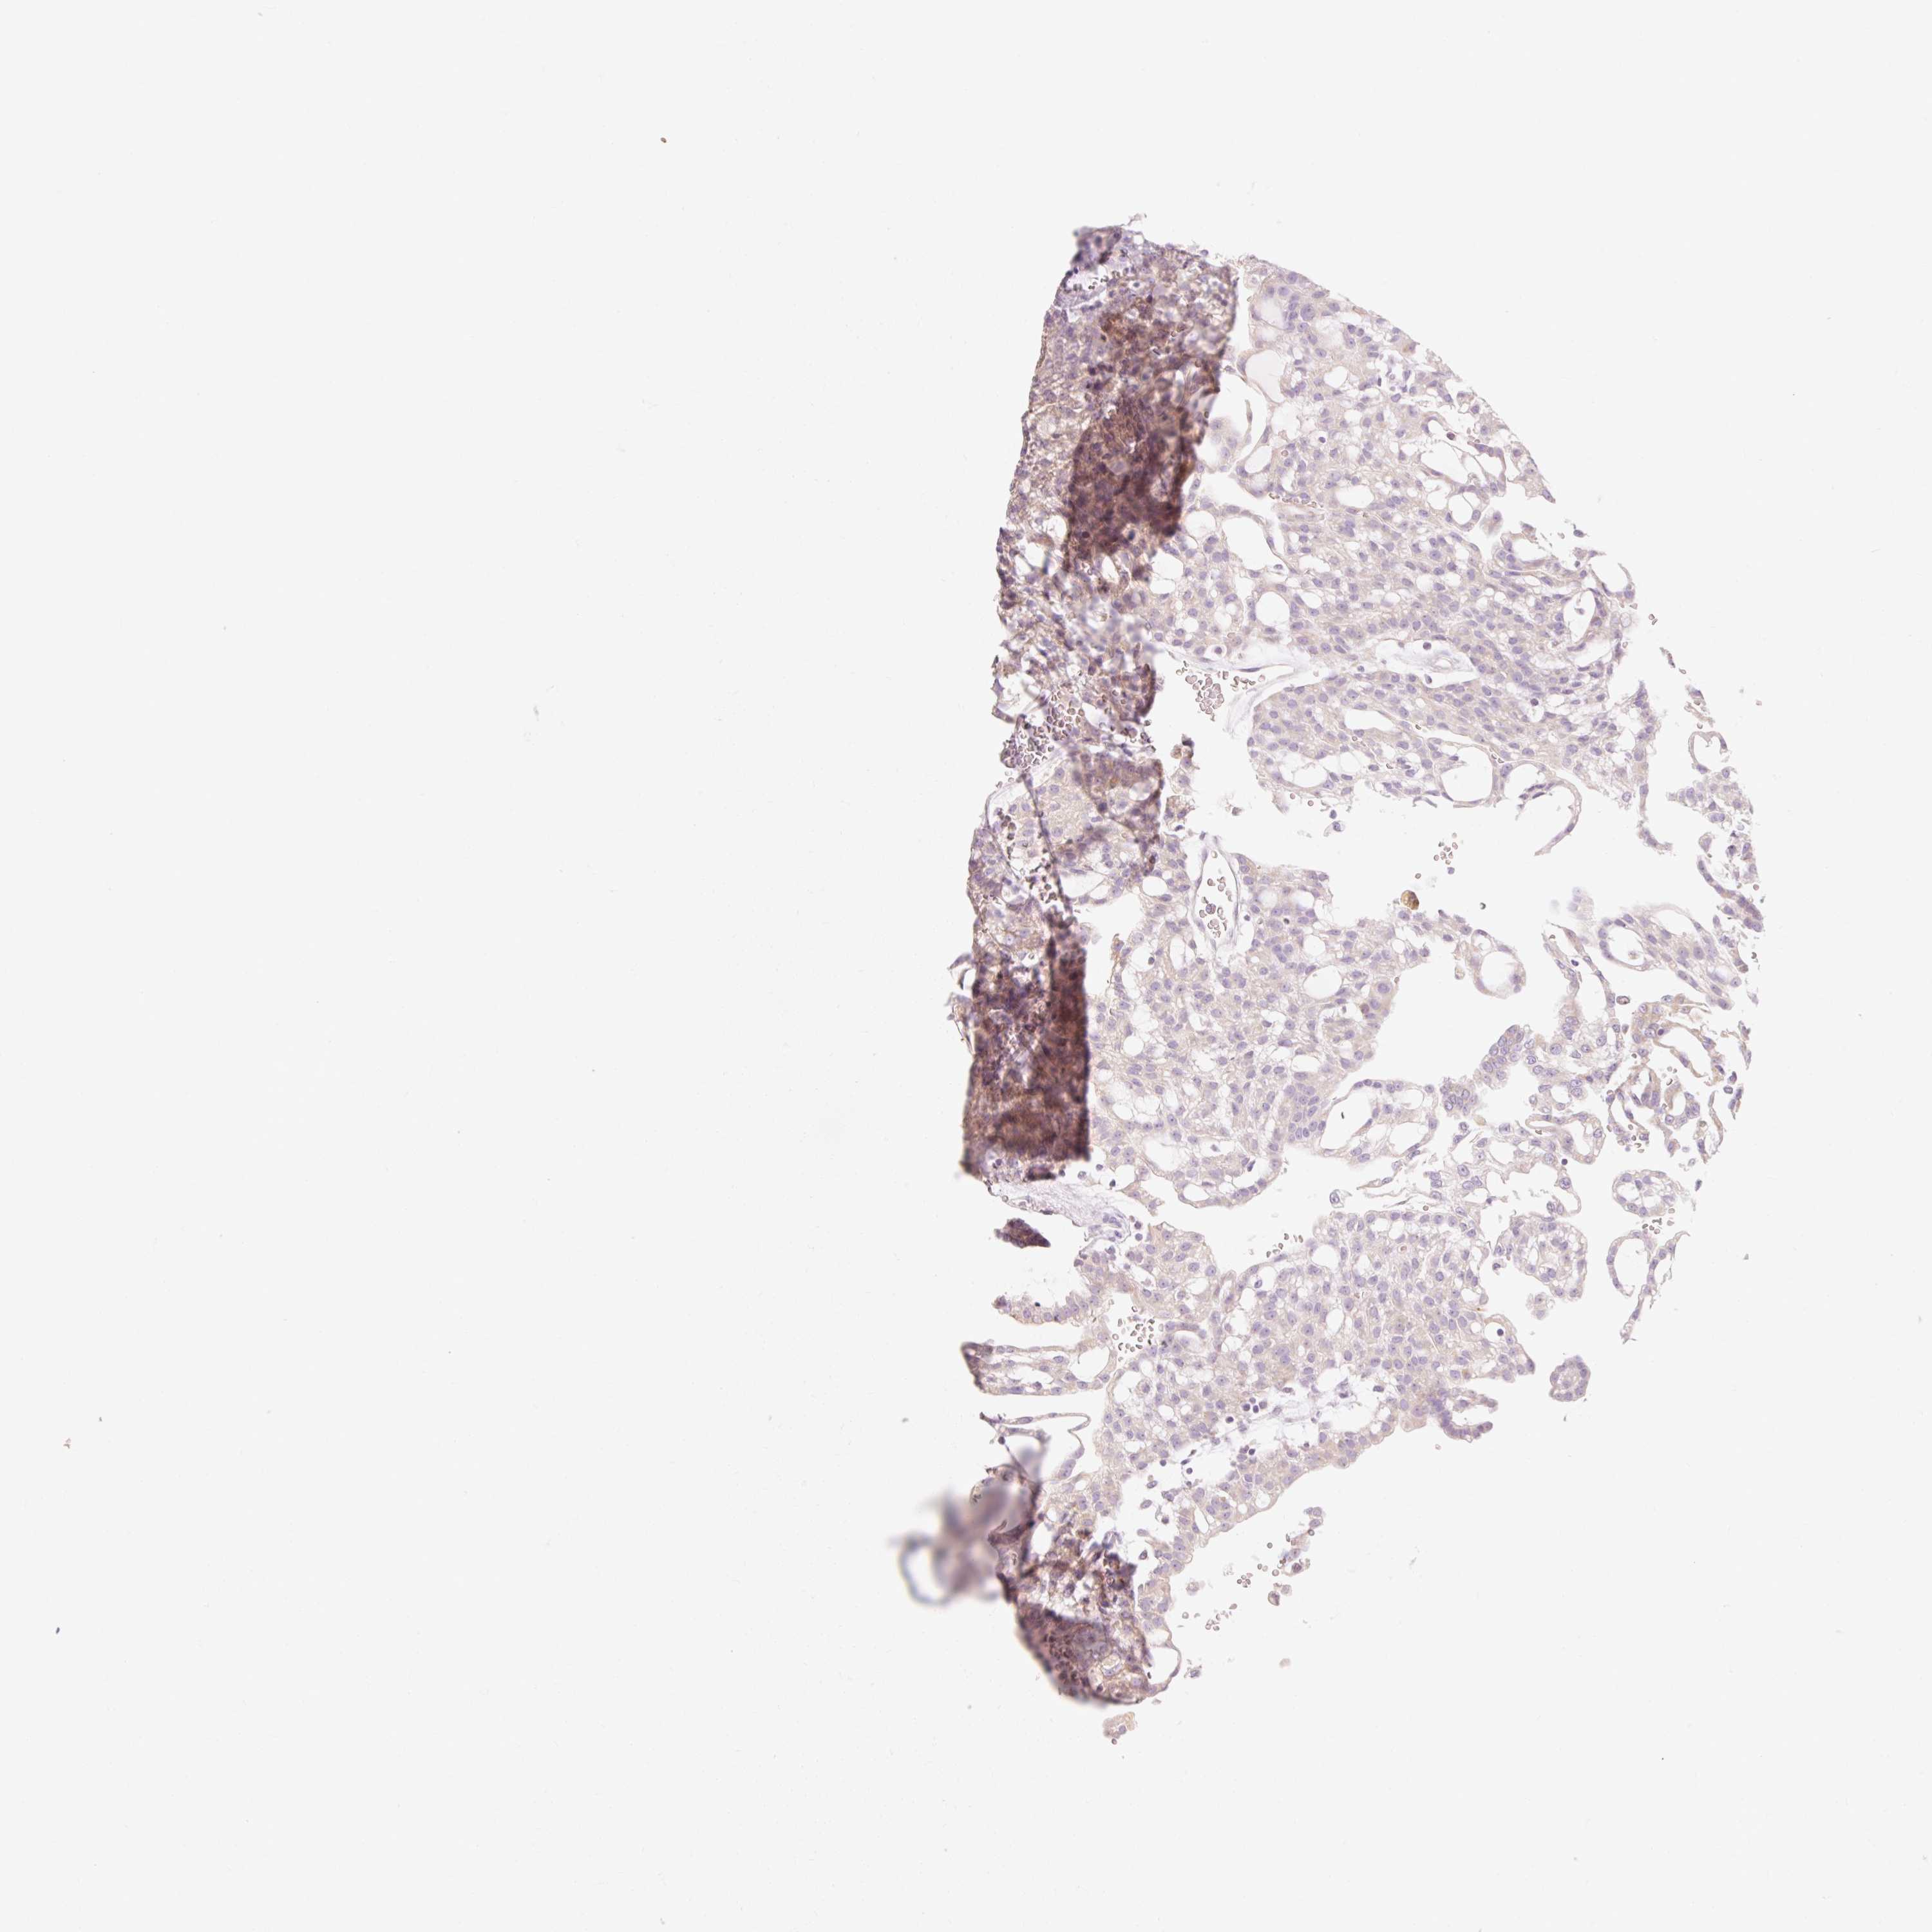

KIDNEY RENAL CLEAR CELL CARCINOMA (VALIDATION) - Interactive survival scatter ploti

The Survival Scatter plot shows the clinical status (i.e. dead or alive) for all individuals in the patient cohort, based on the same data that underlies the corresponding Kaplan-Meier plots. Patients that are alive at last time for follow-up are shown in blue and patients who have died during the study are shown in red.

The x-axis shows the expression levels (FPKM) of the investigated gene in the tumor tissue at the time of diagnosis. The y-axis shows the follow-up time after diagnosis (years). Both axes are complimented with kernel density curves demonstrating the data density over the axes. The top density plot shows the expression levels (FPKM) distribution among dead (red) and alive patients (blue). The right density plot shows the data density of the survived years of dead patients with high and low expression levels respectively, stratified using the cutoff indicated by the vertical dashed line through the Survival Scatter plot. This cutoff is automatically defined based on the FPKM cutoff that minimizes the p-score. The cutoff can be changed by dragging the vertical line or by entering a cutoff value in the square labeled "Current cut-off".

Under the Survival Scatter plot the p-score landscape (black curve; left axis) is shown together with dead median separation (red curve; right axis). Dead median separation is the difference in median mRNA expression between patients who have died with high and low expression, respectively. It is calculated as follows: median FPKM expression of dead patients with high expression - median FPKM expression of dead patients with low expression. This is intended to aid the user in visually exploring custom cutoffs and the associated p-scores and dead median separation.

Individual patient data is displayed and can be filtered by clicking on one or more of the category buttons on the top of the page. Categories describing expression level and patient information include: high, low, alive, dead, female, male and tumor stages. The scale of the x-axis can be toggled between linear and log-scale by clicking on the "x log" button. Mouse-over function shows TCGA ID, patient information and mRNA expression (FPKM) for each patient.

& Survival analysisi

Kaplan-Meier plots summarize results from analysis of correlation between mRNA expression level and patient survival. Patients were divided based on level of expression into one of the two groups "low" (under cut off) or "high" (over cut off). X-axis shows time for survival (years) and y-axis shows the probability of survival, where 1.0 corresponds to 100 percent.

MYO1D is not prognostic in Kidney Renal Clear Cell Carcinoma (validation)

: 16.83

Average pTPM 23.1

Number of samples 100